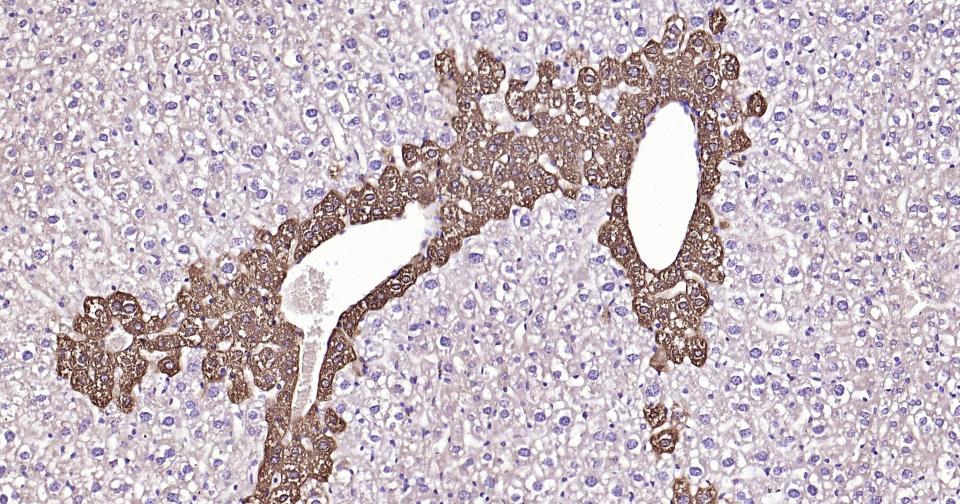

Paraformaldehyde-fixed, paraffin embedded Rat Liver; Antigen retrieval by boiling in sodium citrate buffer (pH6.0) for 15 min; Antibody incubation with Glutamine synthetase Monoclonal Antibody, Unconjugated(bsm-61160R) at 1:200 overnight at 4°C, followed by conjugation to the SP Kit (Rabbit, SP-0023)and DAB (C-0010) staining.